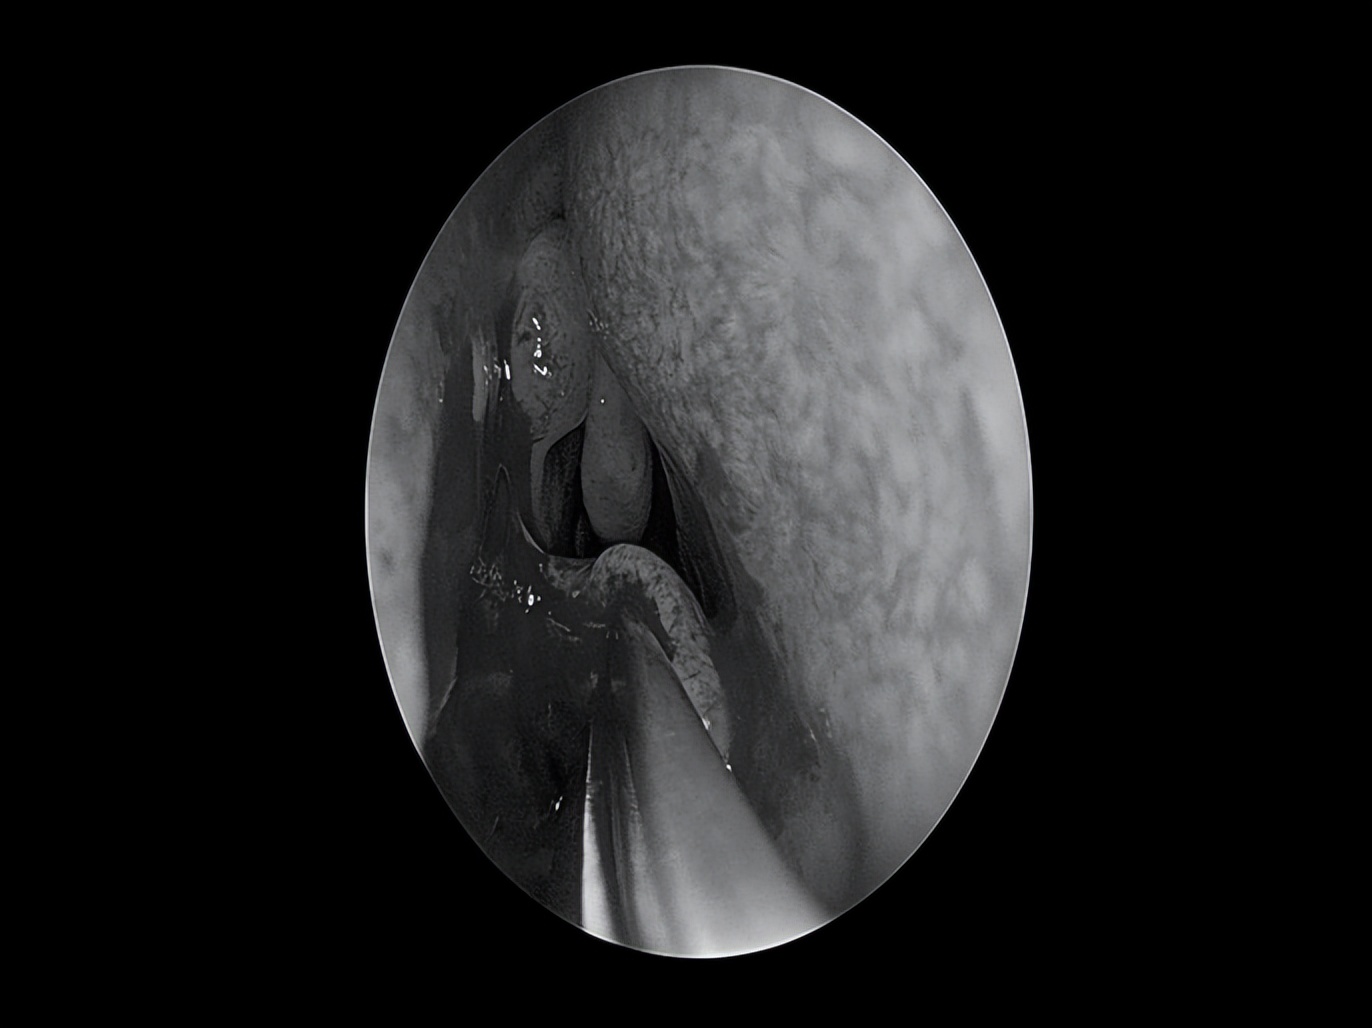

耳内镜检查

双耳鼓膜完整,右侧鼓膜内陷明显,右侧鼓室可见积液